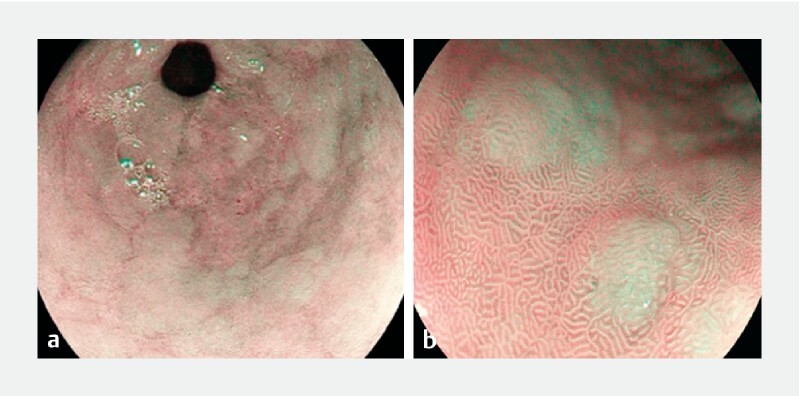

Background and study aims  The light blue crest observed in narrow band imaging endoscopy has high diagnostic accuracy for diagnosis of gastric intestinal metaplasia (GIM). The objective of this prospective study was to evaluate the diagnostic accuracy of magnifying i-scan optical enhancement (OE) imaging for diagnosing the LBC sign in patients with different levels of risk for gastric cancer in a Mexican clinical practice. Patients and methods  Patients with a history of peptic ulcer and symptoms of dyspepsia or gastroesophageal reflux disease were enrolled. Diagnosis of GIM was made at the predetermined anatomical location and white light endoscopy and i-scan OE Mode 1 were captured at the two predetermined biopsy sites (antrum and pyloric regions). Results  A total of 328 patients were enrolled in this study. Overall GIM prevalence was 33.8 %. The GIM distribution was 95.4 % in the antrum and 40.5 % in the corpus. According to the Operative Link on Gastritis/Intestinal-Metaplasia Assessment staging system, only two patients (1.9 %) were classified with high-risk stage disease. Sensitivity, specificity, positive​ and negative predictive values, positive and negative likelihood ratios, and accuracy of both methods (95 % C. I.) were 0.50 (0.41-0.60), 0.55 (0.48-0.62), 0.36 (0.31-0.42), 0.68 (0.63-0.73), 1.12 (0.9-1.4), 0.9 (0.7-1.1), and 0.53 (0.43-0.60) for WLE, and 0.96 (0.90-0.99), 0.91 (0.86-0.94), 0.84 (0.78-0.89), 0.98 (0.94-0.99), 10.4 (6.8-16), 0.05 (0.02-0.12), and 0.93 (0.89-0.95), respectively. The kappa concordance was 0.67 and the reliability coefficient was 0.7407 for interobserver variability. Conclusions  Our study demonstrated the high performance of magnifying i-scan OE imaging for endoscopic diagnosis of GIM in Mexican patients.